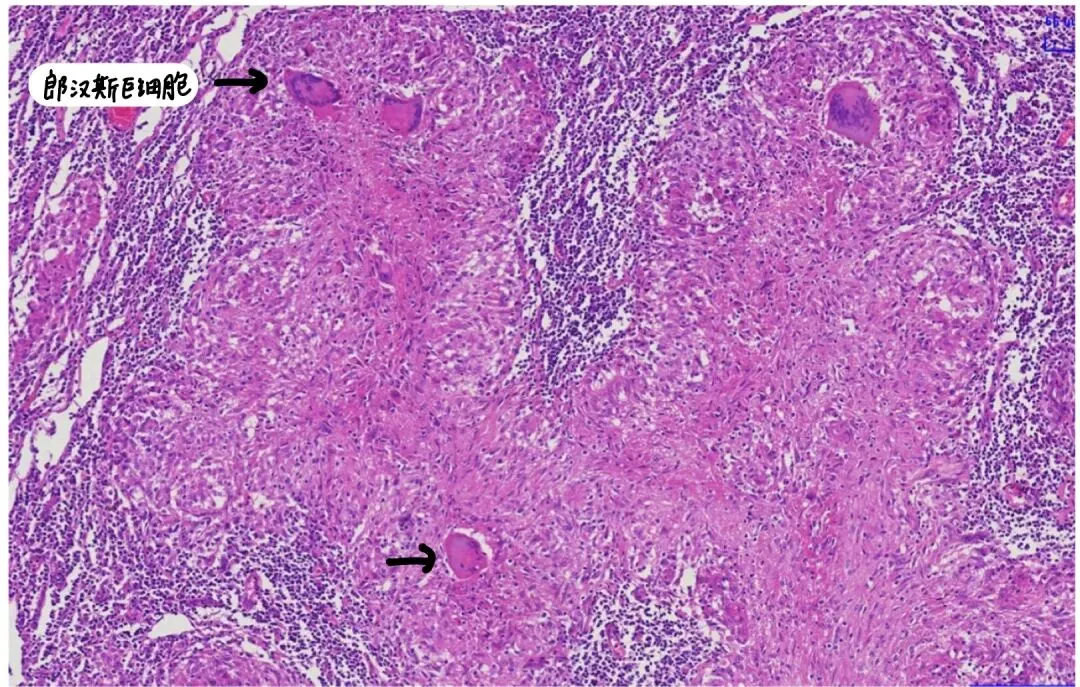

多核巨细胞的细胞核数目可达几十个,甚至几百个;结核结节中的多核巨细胞又称为朗汉斯巨细胞,由上皮样细胞融合而来,其细胞核排列于细胞周边呈马蹄形或环形,胞质丰富;

结核可见干酪样坏死、上皮样细胞、朗汉斯巨细胞、淋巴细胞浸润。

总结一下:巨噬细胞转化成上皮样细胞   → 巨噬细胞或上皮样细胞融合 → 形成多核巨细胞 → 其中一种(朗汉斯巨细胞)的细胞核排列成马蹄环样,理解就是朗汉斯巨细胞是多核巨细胞的一种类型,主要见于特定的感染性或免疫性肉芽肿疾病,比如提示结核等疾病;